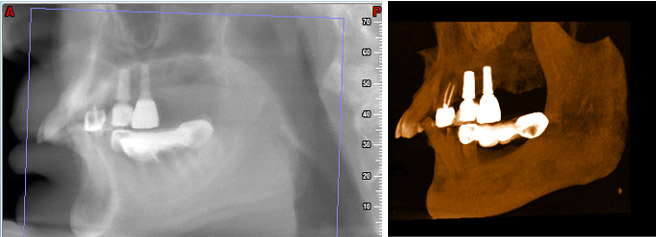

在執行人工植牙之前,須先由專業牙醫醫師檢視植牙條件,因每個人體質與口腔構造因年齡、外觀與先天條件不同,因此植牙步驟會有些許差異。 執行植牙工程之前,需先確認牙脊要有足夠的骨頭,才能進行人工植牙,否則需先進行補骨手術。

像是建築物的地基,人工牙根必須種在堅固的骨頭上,才能發揮良好的固定效果。因此,齒槽骨要夠寬、夠高、夠堅固。然而,缺牙太久或是牙周病等因素,會造成齒槽骨的萎縮,如果萎縮太嚴重,就沒有足夠的骨量可以種人工牙根。此時,在植牙之前,要先進行補骨手術。一般而言,人工植牙手術範圍很小,只需局部麻醉(local anesthesia)。因此,接受人工植牙沒有年齡上限,對缺牙較多的老年人是一大福音。